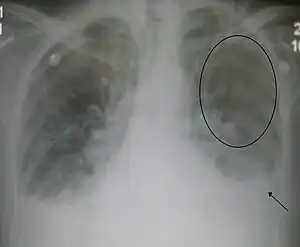

| Acute interstitial pulmonary edema. Note enlarged heart size, apical vascular redistribution ( circle ), and small bilateral pleural effusions ( arrow ). | |